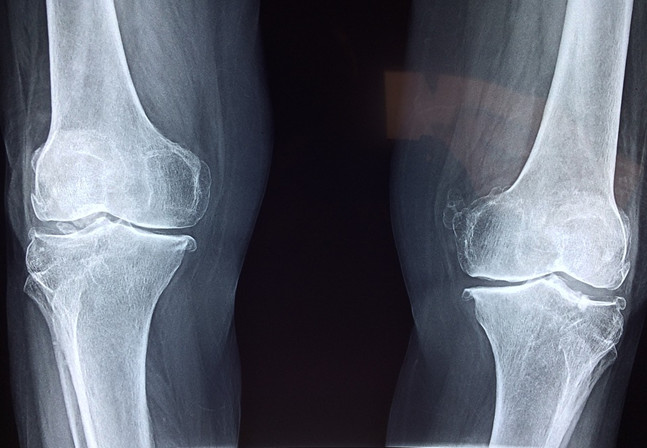

相反,如果身體當中缺少氨糖補給的軟骨會怎么樣呢?在骨骼的摩擦中,原本飽滿健康的軟骨會被磨損,漸漸地保護骨骼的作用就會減弱,失去保護緩沖的動作在完成肢體動作時相互碰撞生痛,也就是許多中老年人遇到腿腳不便的情況了。

為什么是中老年人會遇到這樣的情況呢?事實上人體是能夠自身合成氨糖的,這保證了人體在幼年和青壯年時期的骨骼關(guān)節(jié)不會出現(xiàn)疼痛不便的現(xiàn)象,可隨著年紀增長,身體合成氨糖的速度和數(shù)量隨之減少了,也就開始需要人自行從外界去補充氨糖才能保持關(guān)節(jié)的靈敏舒適。